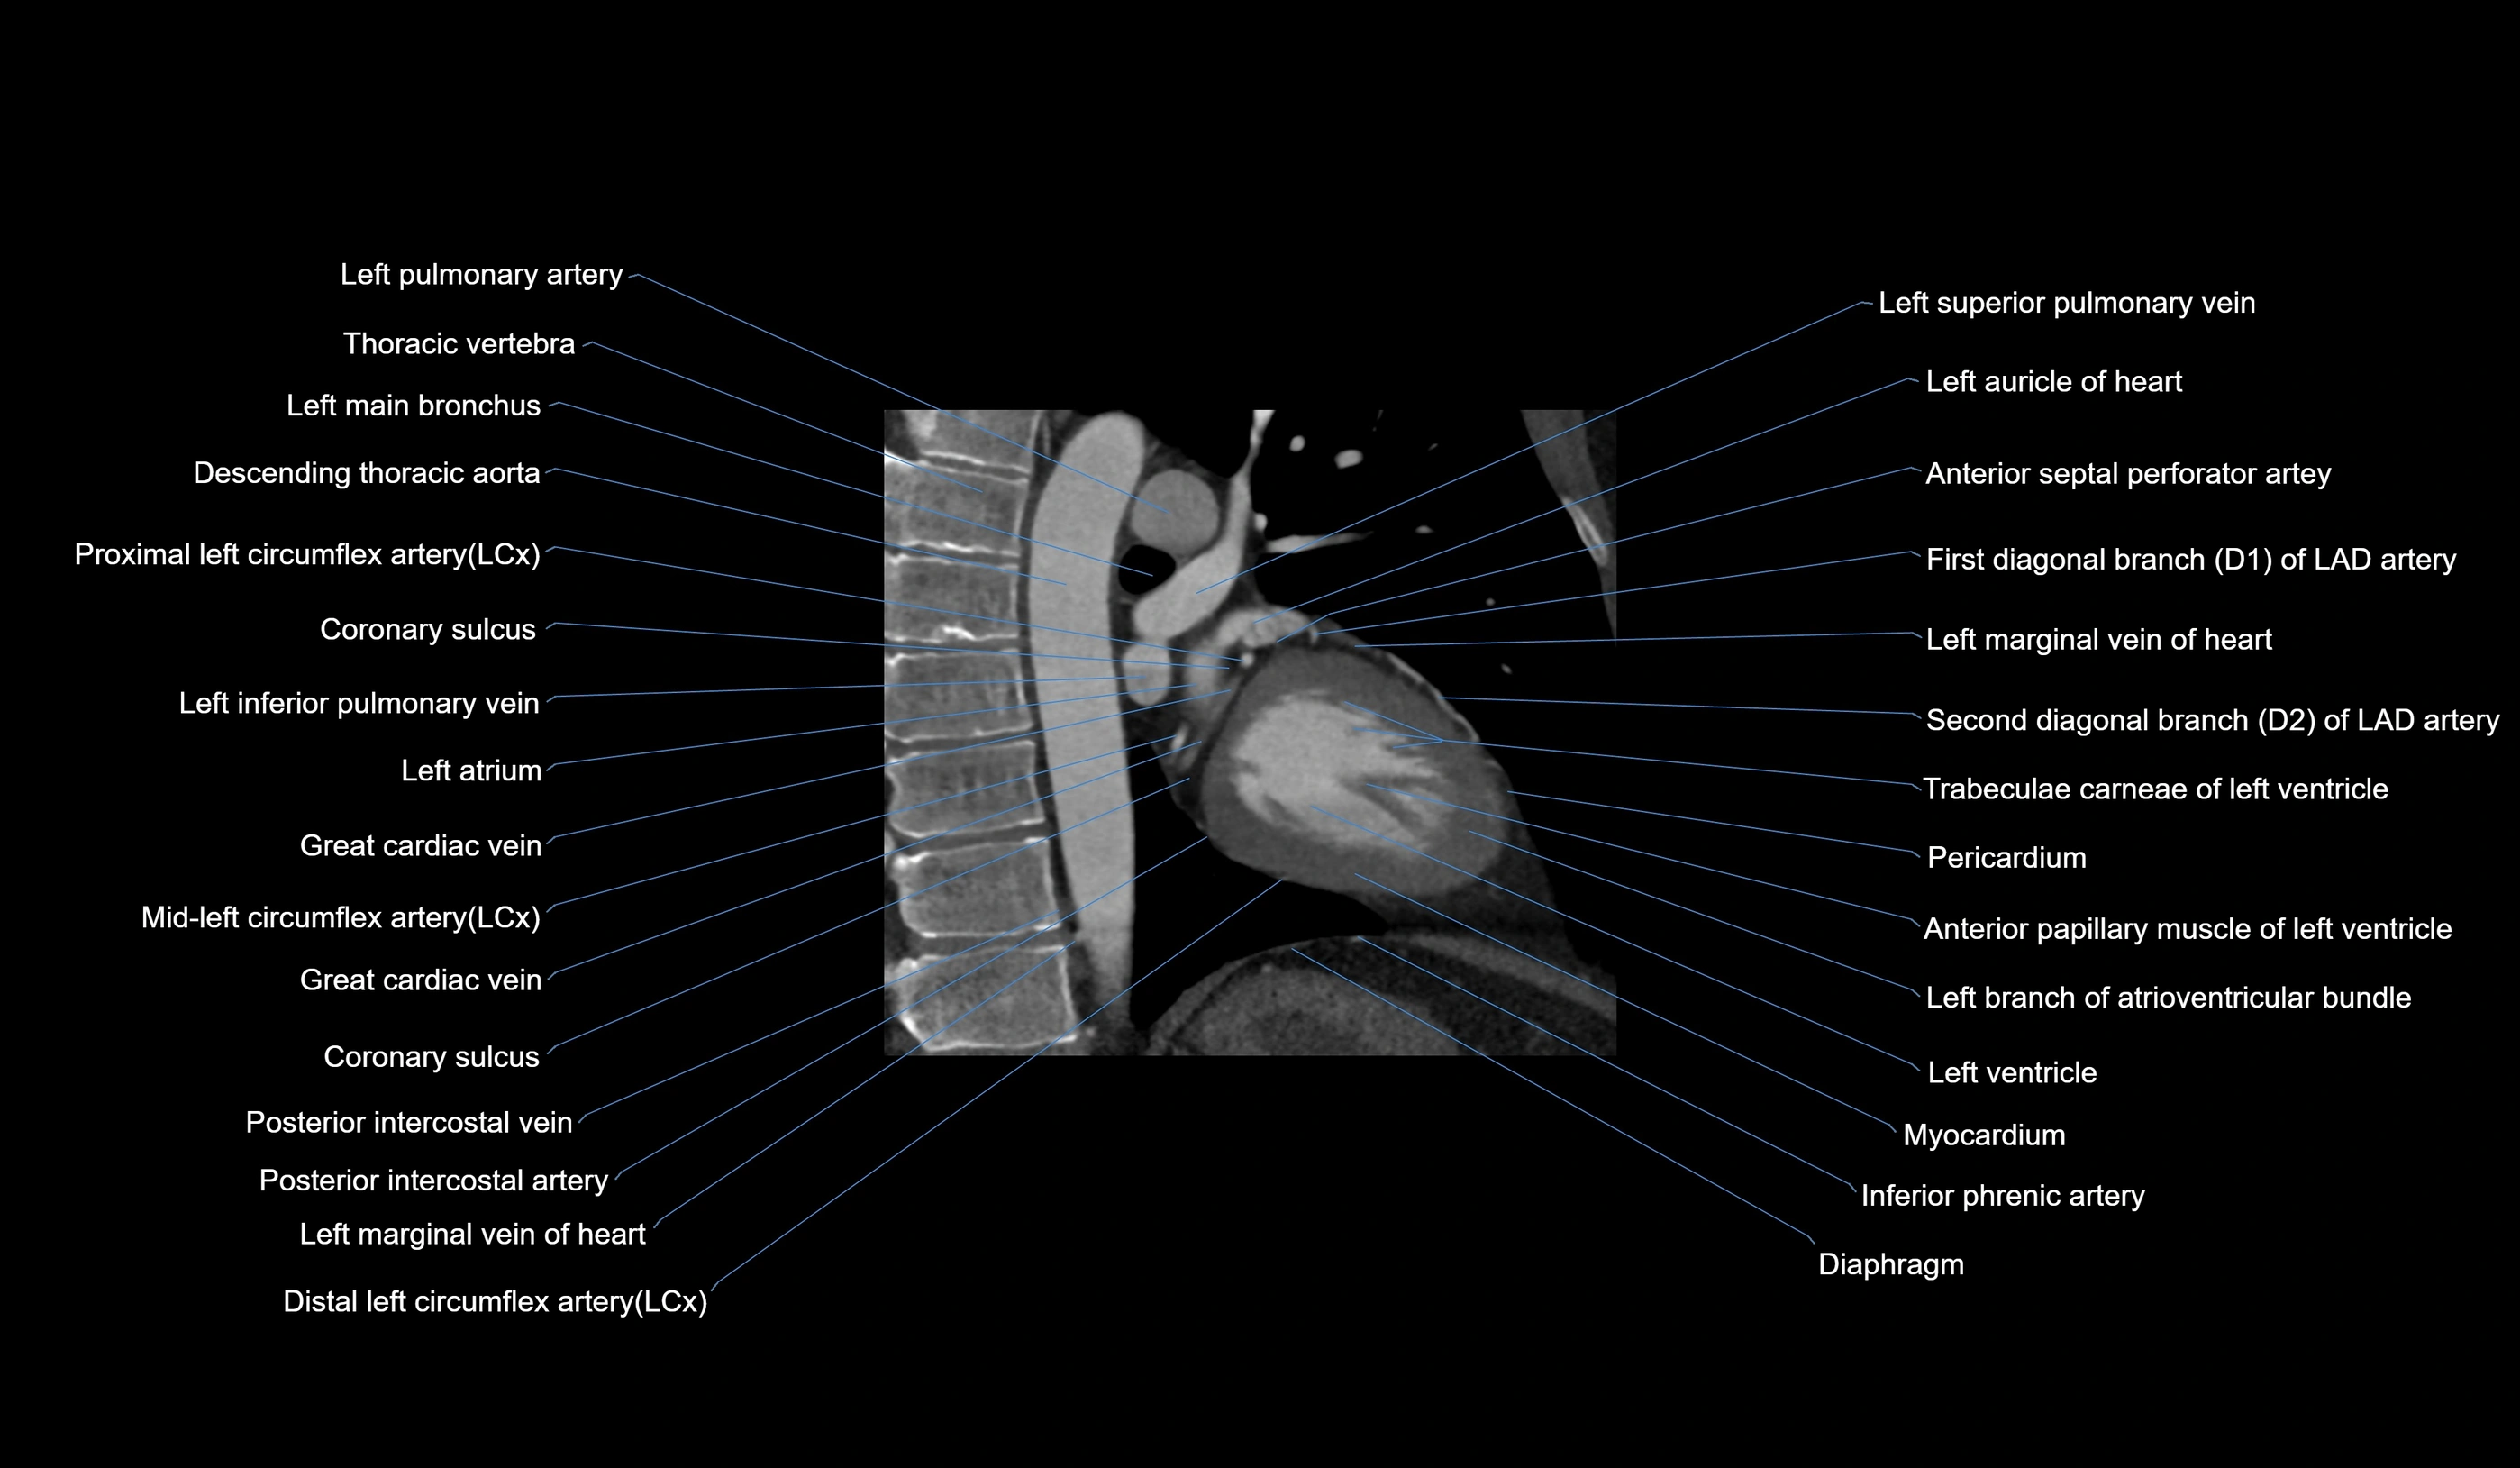

CT images